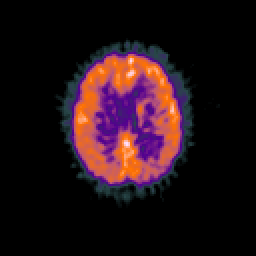

Glioma overlay -- Slice #74

[Home][Help][Clinical] Slice 74